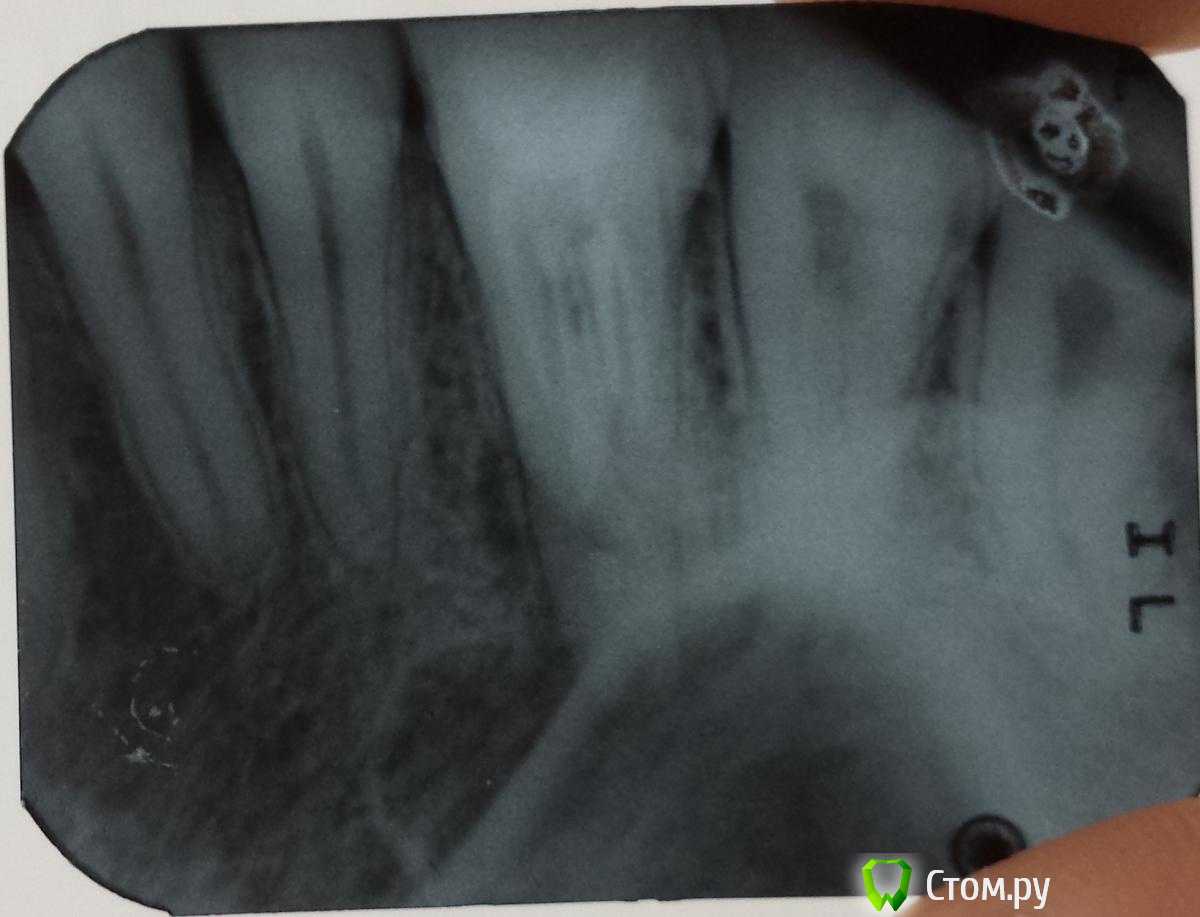

alessandor Опубликовано 8 июля, 2014 Поделиться Опубликовано 8 июля, 2014 Здравствуйте! Очень необходима Ваша консультация. Три недели назад после переутомления и переохлаждения распухла щека, никаких особых болей небыло. Сходил к стоматологу сделали снимок и компьютерное сканирование (КТ). Обнаружено обазование на корне 6 верхнего правого зуба (на снимке третий слева верхний зуб) и в гайморовой пазухе над ним. В 2009 был удален нерв и плохо запломбирован канал. Периодически последнее время при насморке была слабая ноющая боль, а незадолго до опухоли пульсация. Каких либо истечений из носа и насморка небыло, и нет сейчас. Стал принимать антибиотики - опухоль спала, через несколько дней после окончания приема щека снова распухла (может надуло в машине). Сейчас снова принимаю антибиотики (сегодня последний день) - опухоль снова спала. Все это время нос промываю долфином - что заливаю тоже и выходит (чисто). Зуб не шатается, не выпирает, при накусывании не болит (на всякий случай ем на другую сторону). Мне предлагают удаление зуба (говорят будет перфорация) со вскрытием гайморовой пазухи и удалением поврежденной слизистой оболочки. Другие предлагают попробовать полечить. При этом никто никаких гарантий не дает - как получиться. Конечно хочется сохранить зуб и не вскрывать гайморовую пазуху которая меня не беспокоит.Посоветуйте, очень на Вас надеюсь, как поступить, куда обратиться (готов приехать в другой регион), делать надо срочно, опасаюсь что снова распухнет. Могу дополнительно прислать и другие снимки из КТ. Заранее благодарю за ответ! С уважением, Александр. Ссылка на комментарий

dr-krasnov Опубликовано 8 июля, 2014 Поделиться Опубликовано 8 июля, 2014 Картина хронического правостороннего одонтогенного синусита, периапикального абсцесса в области 16 зуба. Показано хирургическое лечение и консультация ЛОР врача. 2 Ссылка на комментарий

alessandor Опубликовано 30 июля, 2014 Автор Поделиться Опубликовано 30 июля, 2014 Сейчас начал лечить зуб. Сняли пломбу, прошли каналы, отказачили через них гной (гноя было много) и заложили туда пасту, поставили временную пломбу на неделю. Говорят зуб залечят точно. Но что будет с кистой на зубе точно сказать нельзя. Возможен ли благоприятиный исход, что зуб залечат и киста тоже уйдет? С уважением, Александр! Ссылка на комментарий